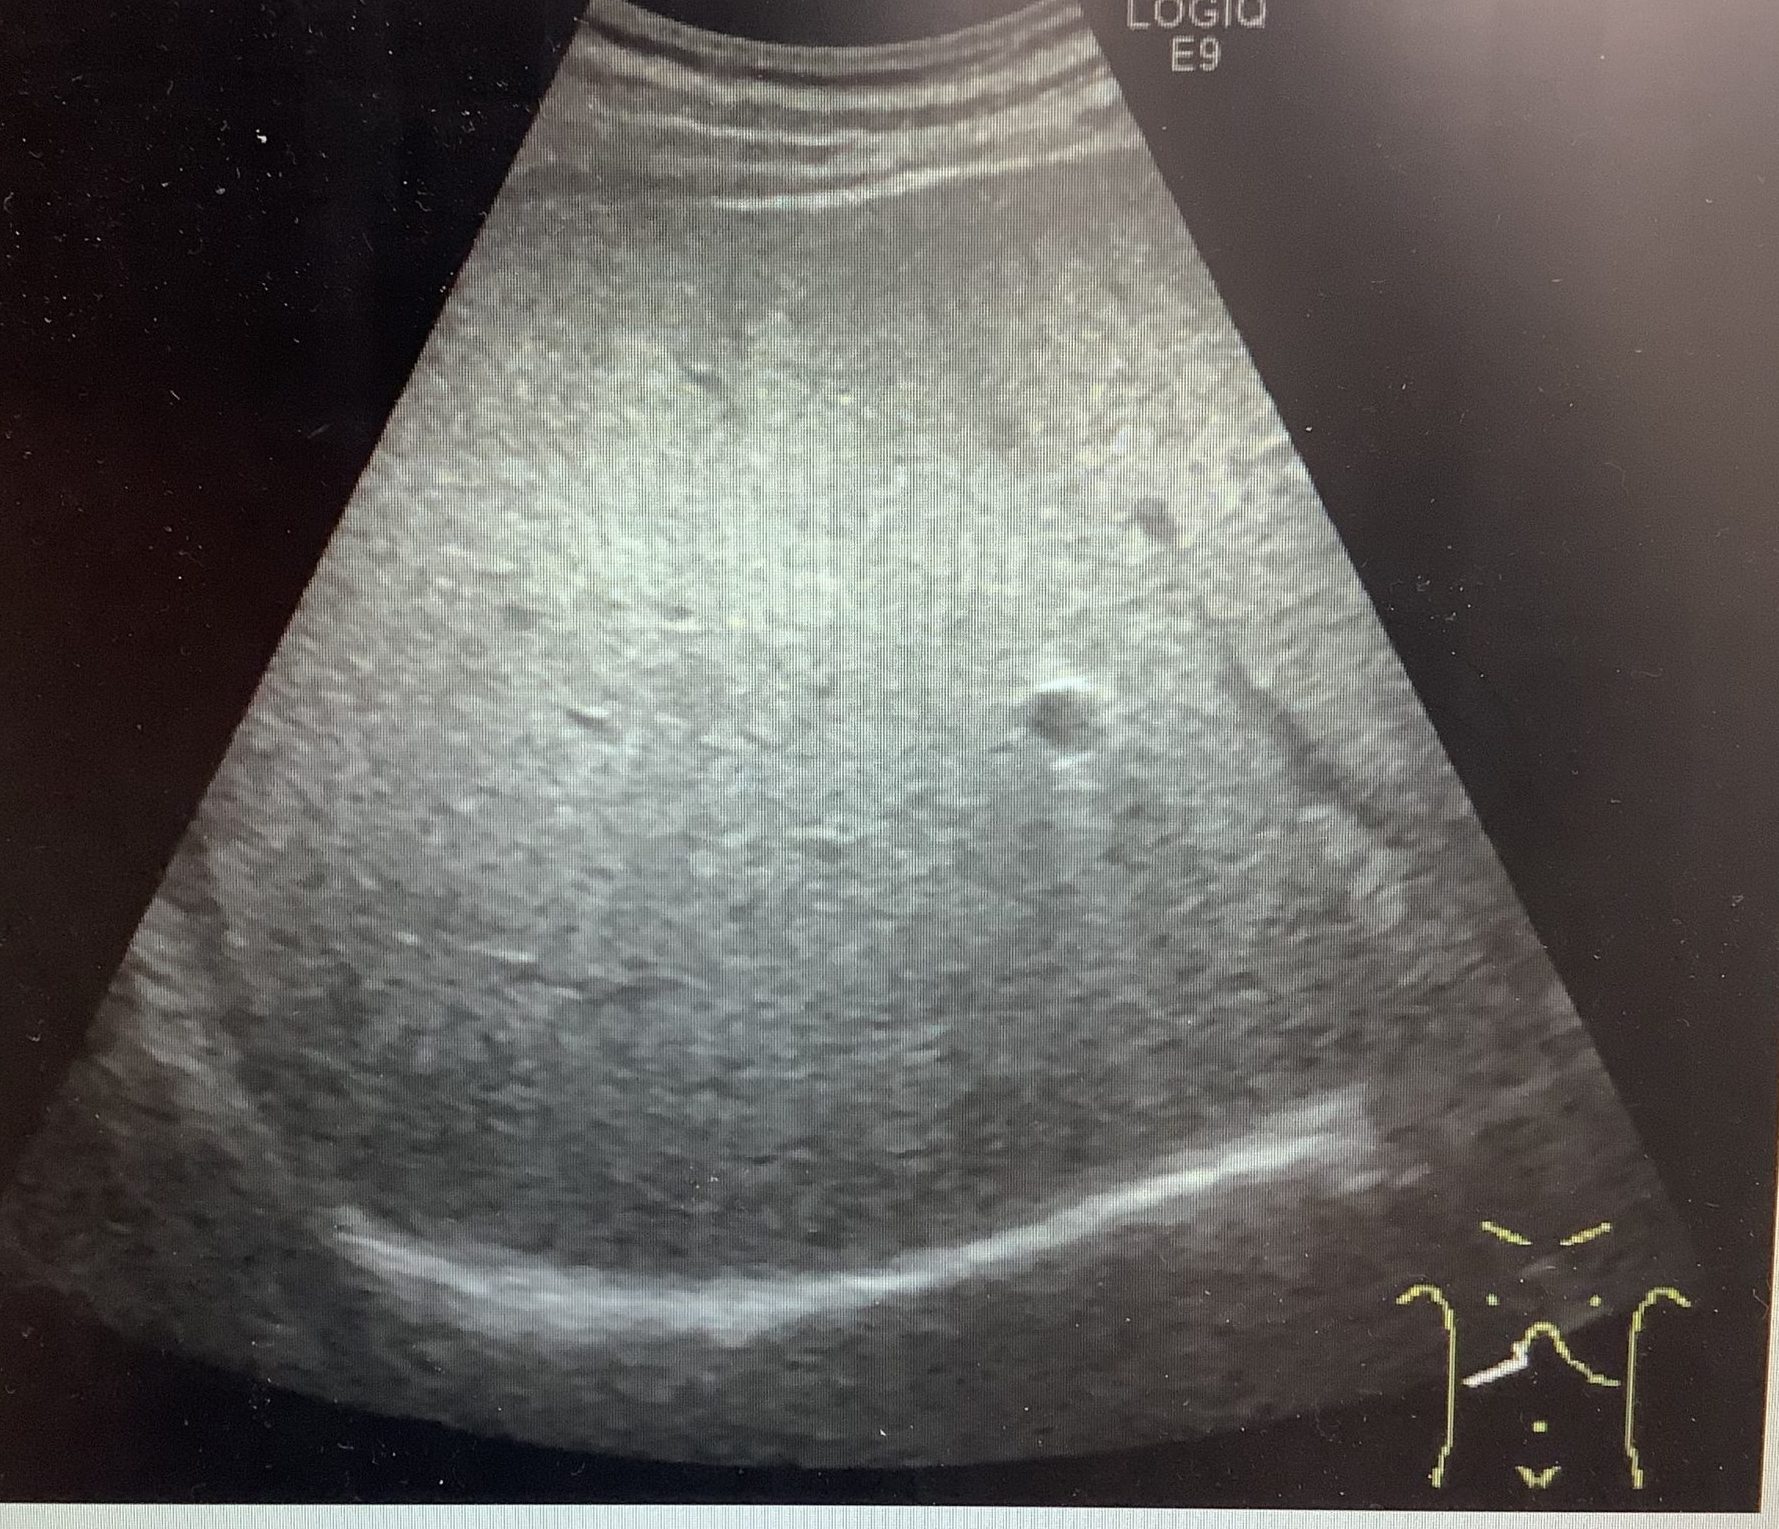

今回は脂肪肝についてお話しします。

人間ドックで腹部エコーを受けていただいた方で、所見に脂肪肝とかえってきた方はいらっしゃいませんか?

脂肪肝とは、肝臓の10%以上に中性脂肪が沈着した状態をいいます。

脂肪肝の原因は、アルコールによるものと、アルコールによらないものがあります。

アルコールによらないものは、ほとんどが肥満によるもので、お酒を飲まない人でも

肝臓の障害が継続して、肝硬変、肝癌へと進行してしまう人がいることがわかってきました。

非アルコール性脂肪性肝炎はメタボリックシンドロームの予防が最も基本的な治療法でもあり、

予防法なのです。

脂肪肝と言われた方は一度かかりつけの先生に相談されることをおすすめします!